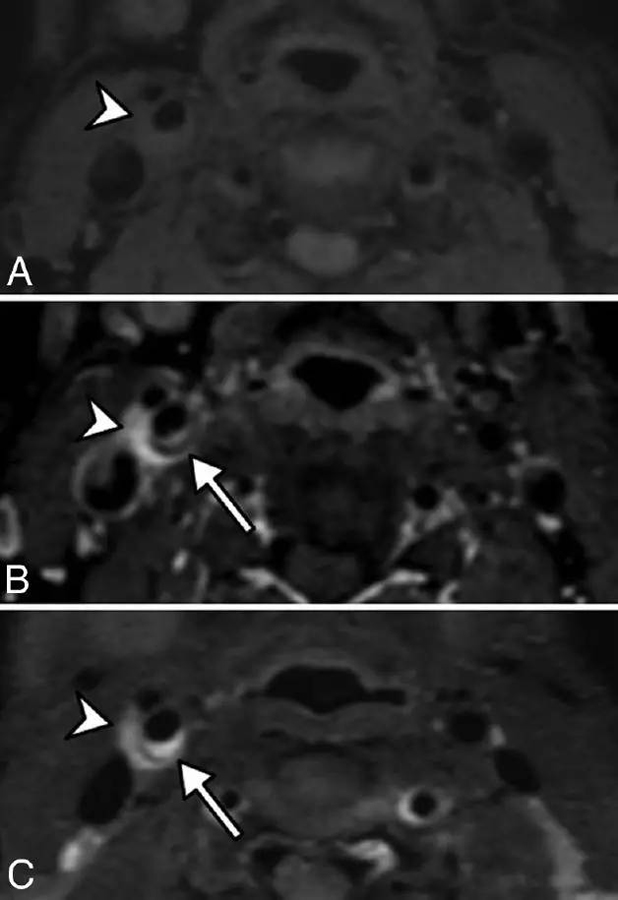

例4:增强前(图A)和增强后(图B)脂肪抑制3D T1 以及3D T2加权(图C)MRI显示颈动脉分叉处短T1和长T2血管周围浸润(短箭头),可见强化。颈动脉后部可见内膜软斑(长箭头)。右侧ICA矢状位曲面重构增强T1(图D)显示右侧颈动脉分叉以及颈总动脉末端和颈内动脉近端可见血管周围浸润(短箭头)。颈总动脉和颈内动脉其他部分未见血管或血管周围异常信号。